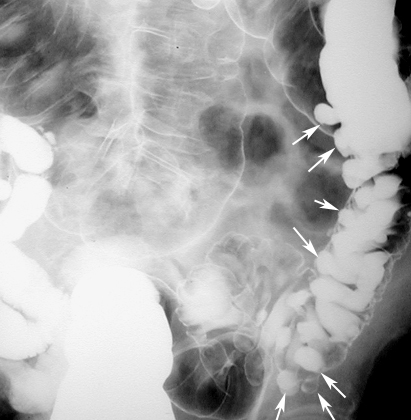

Diagnosing diverticulitis if it involves the pelvis. Endorectal or endovaginal scanning for diagnosing diverticulitis has shown the sensitivity of sonography to be approxi-mately 94%.8,9 Threesonographicfindingsaregenerallyusedtodiagnosediverticulitis:asegmental ... Get Content Here